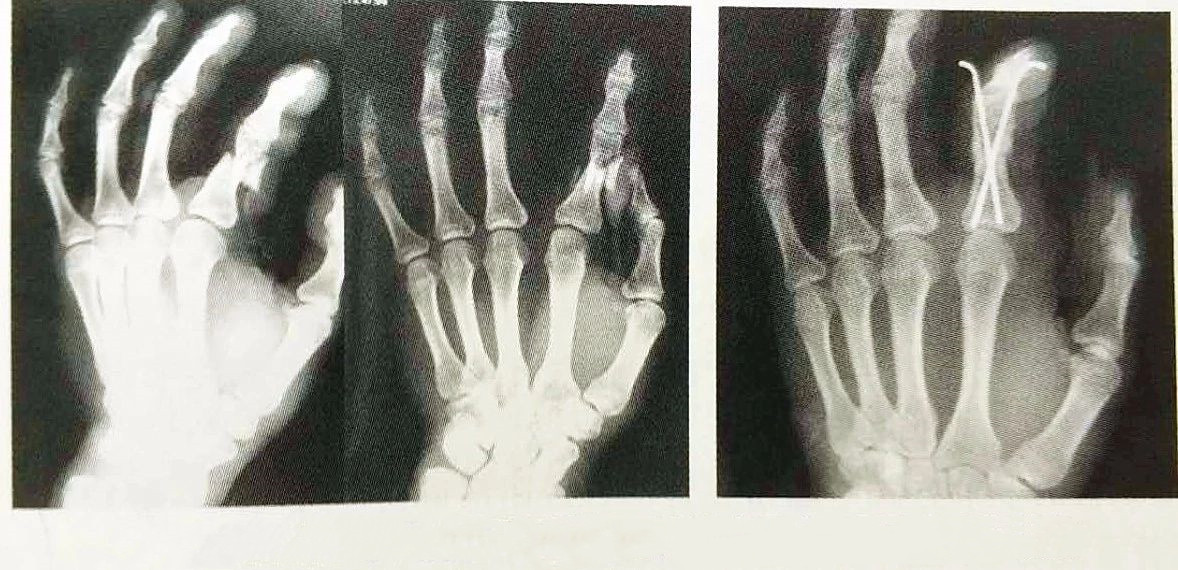

Внутренняя фиксация иглой Киршнера применяется в клинике более 70 лет и является наиболее часто используемым материалом для внутренней фиксации при переломах пястно-фаланговых костей, который прост в эксплуатации, экономичен и практичен, а также является наиболее классическим методом внутренней фиксации, как показано на рисунке. на рис. 4-15.как наиболее часто используемый внутренний фиксатор для лечения переломов рук, он до сих пор широко используется.

С быстрым развитием современных методов и оборудования для внутренней фиксации внутренняя фиксация спицами Киршнера становится все более и более совершенной, и большинство из них можно фиксировать без пересечения сустава, с небольшим повреждением мягких тканей и сухожилий вокруг сустава и не влияя на раннюю послеоперационную тренировку суставов.С помощью рентгеновского аппарата С-дуги в некоторых случаях также можно добиться удовлетворительных результатов путем закрытой репозиции внутренней фиксации спицами Clinique, что дополнительно снижает повреждение местных мягких тканей и влияние на кровоснабжение конца перелома, таким образом способствовать заживлению перелома.